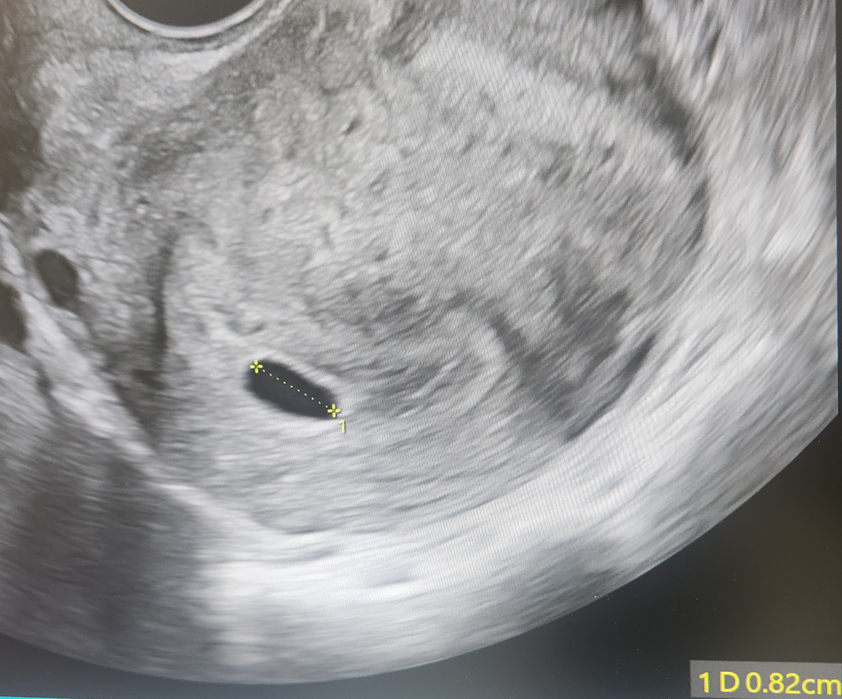

임신 6주차와 7주차 초음파에서 난황이 보이지 않아, 병원에서는 일주일 뒤 한 번 더 확인해보자고 했습니다.

아기집은 여전히 비어 있었고, 크기도 지난주보다 오히려 조금 줄어든 상태였습니다. (9.4mm → 8.2mm)

이런 결과를 바탕으로 병원에서는 계류유산이라는 진단을 내렸습니다.